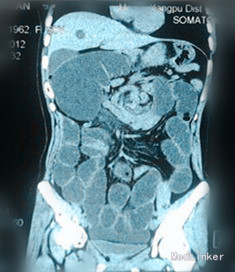

查体:生命体征平稳,体温37.5°C。未见黄疸;Murphy氏征(-);麦氏点无压痛、反跳痛;腹部明显膨隆,脐周压痛,肠鸣音活跃,可闻及气过水声。 辅查:腹部B超:胃及肠管扩张。 腹部立卧位片示:部分肠腔积气积粪伴小液平。 CT 示:肠扭转,回盲部异位并扩张。

诊断:腹痛查因:消化道穿孔? 治疗:入院后予禁食、胃肠减压、灌肠、抗感染、解痉、补液、支持等治疗,12 h 后病人腹痛无缓解,未排气排便,急诊查电子肠镜提示:横结肠近肝曲肠腔闭塞,肠镜无法通过。急诊在全麻下行剖腹探查术,术中探查见全小肠扭转并扩张,升结肠先天性游离并扩张,距屈氏韧带约10 cm 处小肠系膜根部有一裂隙,直径4 cm,升结肠穿过裂隙后致肠管被卡压扩张形成内疝,将小肠扭转复位并送回卡压升结肠,关闭小肠系膜裂隙。手术顺利,术后恢复良好出院。

先天性小肠系膜裂孔疝是一种罕见的疾病,是肠管通过先天性的小肠系膜裂孔而形成的腹内疝。本病临床表现为急性闭袢性肠梗阻,术前诊断非常困难。往往是术后,根据术中发现再结合术前的腹部CT 和动脉造影才找到诊断的依据。在CT 图像上,小肠系膜裂孔疝表现为扩张聚集的小肠袢,直接与前腹壁相邻,二者间无网膜覆盖,即在扩张的小肠壁和腹壁间没有脂肪组织存在。横结肠通常向下移位,有时可以将升结肠和降结肠向内侧推移移位。提醒各位临床医生,对一些不明原因且病情发展迅速的肠梗阻病人,应警惕有腹内疝的可能。